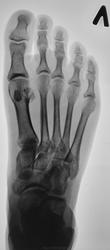

Молодая женщина. Беспокоят боли в ступнях по подошвенной поверхности, больше слева.

Правая стопа сделана больше для сравнения.

Остеохондропатия сесамовидной кости 1 пл/фал.сустава левой стопы.

Спасибо. Но, вот почему она увеличена?

Весьма патогномоничной является рентгенологическая картина третьей стадии заболевания - стадии фрагментации. Пораженный отдел кости уже не дает гомогенной тени, а состоит из нескольких темных бесструктурных изолированных фрагментов неправильной формы. Светлые участки, на фоне которых видны эти фрагменты, соответствуют разрастаниям соединительной ткани и хряща между некротическими массами. Высота пораженного отдела кости уменьшается. Длительность третьей стадии составляет от полугода до двух с половиной лет, а иногда и более. Вероятно Валентин Львович, дама не сидит, а ходит, постоянная нагрузка веса тела делает свое дело.

Фрагменты с увеличением.

А почему остеохондропатия? Раз пациентка непоседлива и много ходит -тогда может это просто перелом,по типу маршевого или стресс-перелома,от нагрузки.Перелом с расхождением отломков ,пытается срастись:))-но получается -не очень ,так как покоя ноге мадам не дает.

И почему кость (сесамовидная) так увеличилась в размерах?

"На рентгенограмме-типичная дезорганизация структурного рисунка несколько иногда увеличенной косточки с фрагментацией её тени.Регенеративные явления выражены незначительно,полного восстановления стуктуры не бывает"-С.А.Рейнберг т2 стр286.      (несколько иногда( в тексте))-это вероятно в данном случае.

Правую никак не смог разглядеть надо бы обработать получше. в левой старая связочная травма сустава Шопара, постттравматический небольшой подвывих пяточно-кубовидного сустава, следы почившего гемартроза там же. Травма эта не с лестницы вперед упала?

несросшийся перелом сесамовидной слева